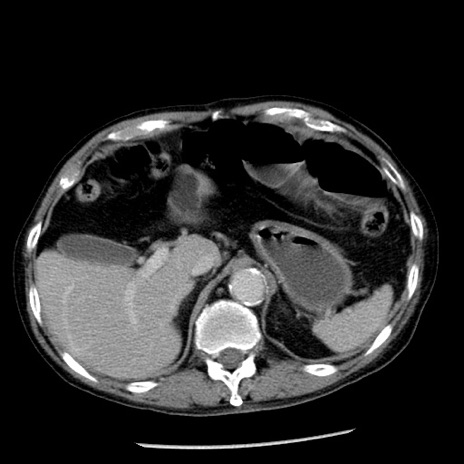

冠状断像

症例26(横断像)

【症例】80歳代男性

【主訴】嘔吐

【現病歴】昨晩2回嘔吐あり、今朝になっても嘔吐あり。来院。

【既往歴】胃潰瘍

【身体所見】意識清明、BT 37.6℃、BP 166/95mmHg、HR 100bpm、SpO2 97%、腹部:平坦・軟、腸蠕動音聴取良好、圧痛なし。

【データ】WBC 21900、CRP 1.46